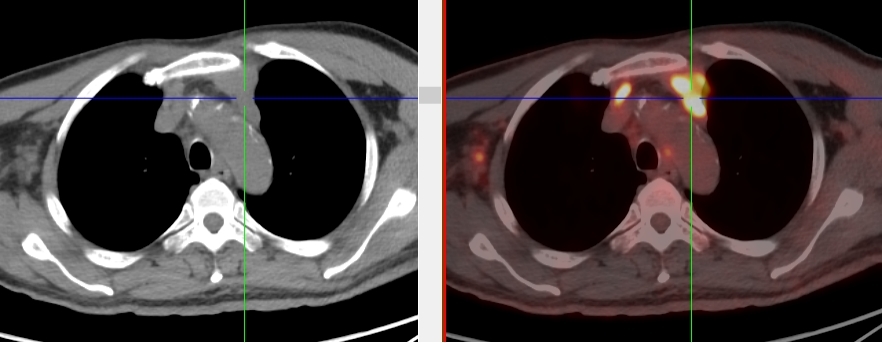

頸胸部多處代謝異常病灶

完善胸部強化CT考慮縱隔MT并縱隔、右腋窩及雙肺門多發(fā)腫大淋巴結,后行超聲引導下行右腋窩腫物穿刺活檢術,病理首先考慮惡性腫瘤,因穿刺組織局限,腫瘤細胞成分過少,不能明確診斷。

完善PET/CT檢查示:右側腋窩、雙側中下頸部、縱隔、雙側肺門多發(fā)MT,建議淋巴結活檢。后患者行右腋窩淋巴結切除活檢術,經北京大學第三醫(yī)院病理科會診示:右腋窩淋巴結惡性腫瘤,呈淋巴竇內生長模式,瘤細胞呈上皮樣,異型性明顯,伴中性粒細胞浸潤。結合病史及免疫組化,考慮為SMARCA4(BRG1)缺失的胸部腫瘤,伴神經內分泌標記表達。

本例為罕見病理類型的腫瘤,影像學表現無明顯特異性,診斷困難。強化CT和穿刺病理已基本明確為惡性腫瘤,行PET/CT檢查一是為了全身檢查,完善分期,二是根據PET代謝情況指導進行生物靶區(qū)活檢,進一步明確病理診斷。最終,PET/CT除縱隔病變外發(fā)現更多頸胸部淋巴結代謝異常,綜合考慮后對腋窩淋巴結進行切除活檢,最終得到病理證實。